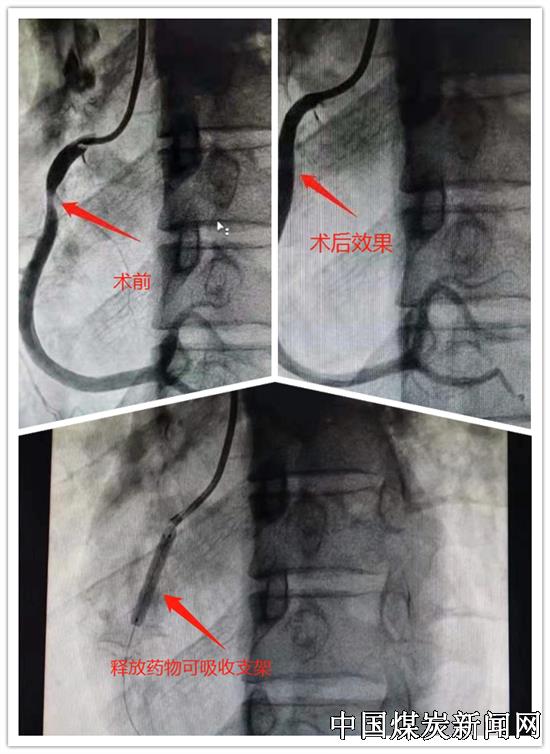

【本网讯】近日,华北医疗集团峰峰总医院北院区心内科团队,成功为一名青年患者,实施IVUS(血管内超声引导)下Neovas生物可吸收支架植入术,术后患者胸痛症状明显好转。此项技术的顺利完成标志着峰峰总医院向本领域技术高峰迈进了一大步!

青年患者,司某,35岁,因间断发作胸痛4个月,在家难以忍受,来北院区心内科就诊。诊断为不稳定心绞痛,发作时明显缺血心电图改变,经冠脉造影术显示胸痛症状和心电图改变由右冠近段80%狭窄引起。科主任赵军峰考虑司先生还非常年轻,建议做冠脉支架手术,由于传统药物支架术后会给患者带来很多不便,因此,组织全科医生进行病例讨论,针对患者对体内置入异物存有排斥心理,认为患者还比较年轻,并且具有药物可吸收支架适应症。最后,决定为患者实施药物可吸收支架置入术。

科室医疗团队按照讨论的治疗方案紧张有序地做好术前准备,大家紧密配合,尹威、魏鹏辉主治医师,导管室技师李志刚,主管护师郑银霞,首先为患者进行了ivus检查,仔细鉴别分析血管内斑块的性质及成分。然后在血管内超声引导下,安全置入生物可降解新型支架,术后造影显示血管狭窄症状消失,真正达到了精准治疗的目的,最终司先生的手术顺利成功完成。术后司先生已无胸闷、胸痛症状,已于近日出院。据悉,此项IVUS引导下生物可降解支架植入术,在省内属于本领域内的前沿技术,在邯郸市处于领先地位!